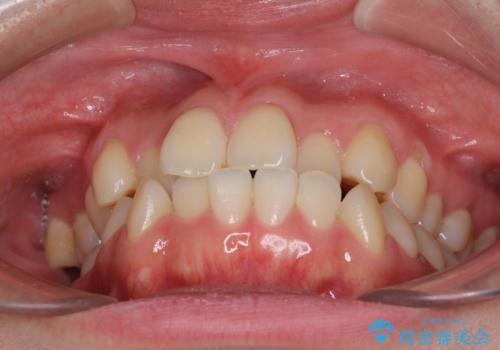

- 前歯のデコボコとクロスバイトを気にして来院された患者様です。

骨格的に下顎が前方位の受け口傾向であり、それが原因でクロスバイトとなっていました。

なお、右奥の歯が180度回転した状態で萌出しており、こちらは改善困難なため、そのままの向きで配列することとしました。